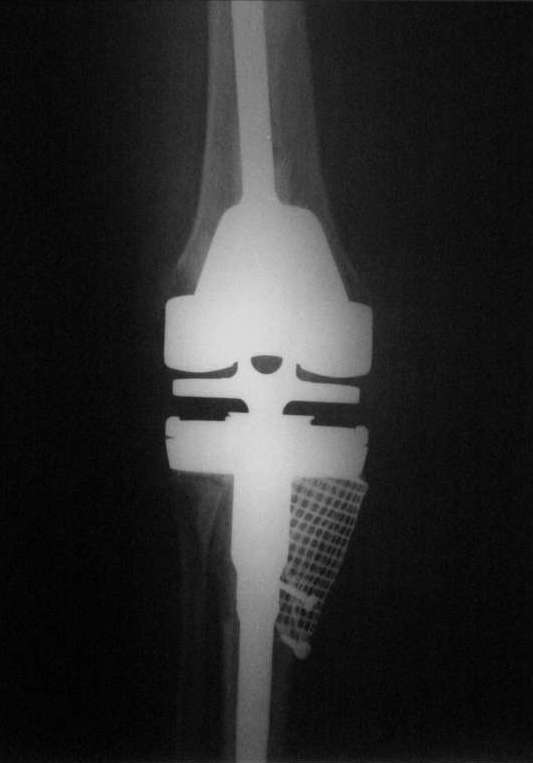

Уважаемые коллеги, В начале марта просил совета, что делать. Вот то, что получилось и снимки

во время операции.С уважением, Римашевский Д.